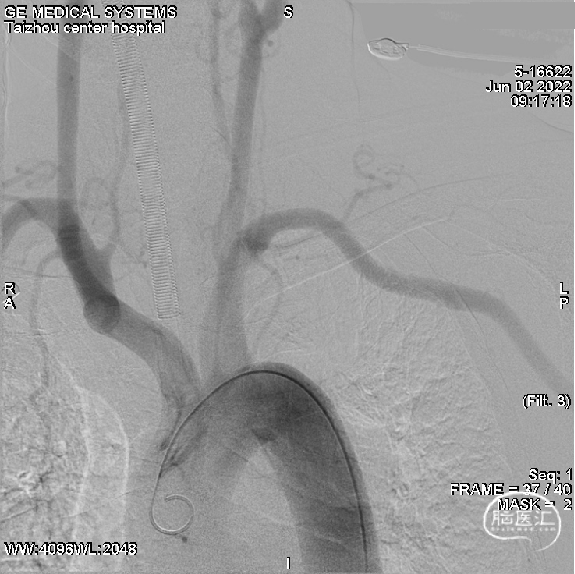

主动脉弓造影:II型弓

左侧椎动脉造影:正侧位

左侧P2远端显影差,基底动脉尖部(左SCA起始处)充盈缺损,左SCA不显影。

右侧颈总动脉造影:正侧位

左侧颈总动脉造影:正侧位

未见血流经左PCoA代偿到同侧PCA。